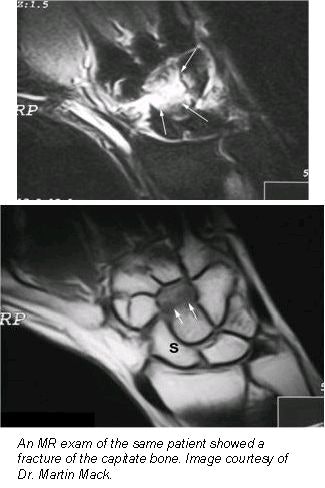

The same evaluation team then reviewed the MRI results and found scaphoid, radius, and other fractures in 20 of the patients, with 36 showing no fracture. There were false-positive results on plain radiographs in more than half of the patients. False-negative diagnoses of the radiographs were found in 6 cases. Between MRI and the radiographs, the diagnostic agreement of the observers was 44.6% and 55.4%, respectively.

In more than a third of the patients, MRI allowed for the detection of additional injuries to soft tissue. Bone bruises were found on 15 patients, discus lesions were observed in 7, and ligament injuries and ligament avulsion were found in 5 and 8 patients, respectively. In addition, 13 patients were diagnosed with joint effusion, and cysts were discovered in 3 patients.